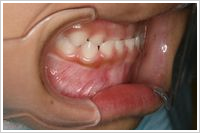

●4歳5ヶ月(治療前の受け口)

●4歳11ヶ月(治療開始から6ヵ月後)

ムーシールドで改善された正常な歯並び

さらに約6ヶ月間ムーシールドを使用して経過観察します

取り外し式の矯正装置であるムーシールドを使用しました。昼間1時間と就寝時に装着します。最初の1~2週間はよだれがだらだらと出てきたり、うまく装着できず口から飛び出すことがありましたが、その後は慣れてきて朝まで口の中に入っているとのことでした。月に1回装置の調整を行いました。6ヶ月後には受け口が改善され正常な咬み合わせになりました。